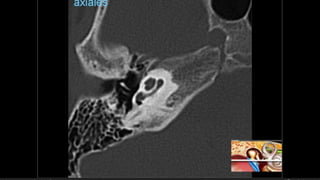

Evaluación Imagenologica

• #38 Izqu. AXIAL-- fxLongitudinal perdonan la capsula otica (laberinto oseo) Centro AXIAL fx trnasversa lascuales tperdonan el lab erinto oseo Dere: MIXTA – tmp perdona

• #52 AXIAL Frctua canal carotideo